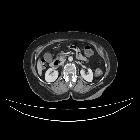

CT

Focal outpouching of the duodenum adjacent to the papilla (usually 2 part of the duodenum) causing compression of the CBD.